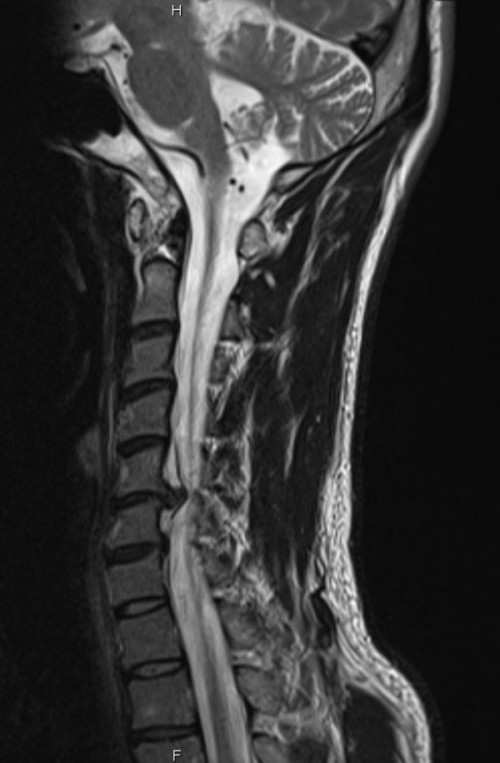

I’ve looked at his MRI scan and it looks like exactly like pictures below: